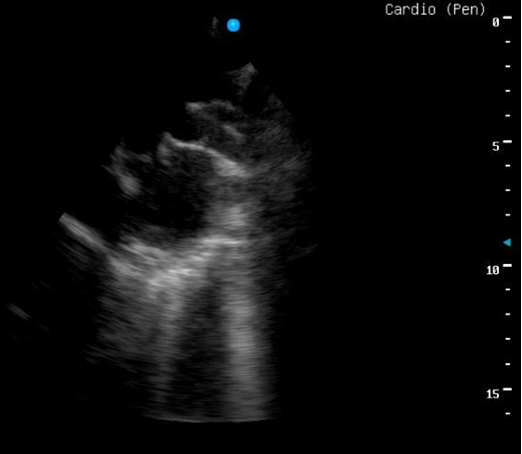

During her follow-up with cardiologist, no any additional echocardiographic change was noticed. Only during physical examination found to have grade 4 thrill with radiation to the neck. She was arranged for another cardiac catheterization for trail of closure once occluder devices became available in our center after 15 months from first catheterization. During the second catheterization aneurysmal change seen at the pulmonary end rather than aortic end of the PDA with aortic end 3.4 mm* midpoint 7.5 mm* pulmonary end 15.9 mm (Figure 2), so decision was made for surgical closure rather than trial of occlusion with a occluder devices (Figure 3).

Figure 2: Second angiography with lateral aortogram showing dilated pulmonary end of patent ductus arteriosus.